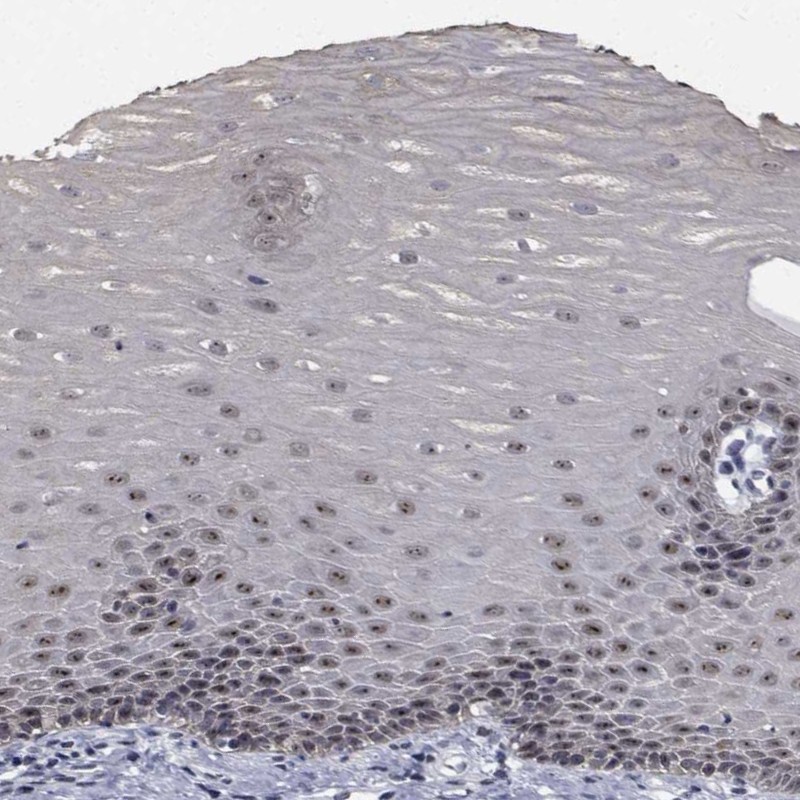

Immunohistochemical staining of human esophagus shows moderate nucleolar positivity in squamous epithelial cells.